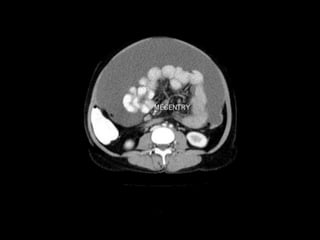

Small Bowel.

Central position

in the abdomen

Valvulae

conniventes -

mucosal folds

that cross the

full width of the

bowel

(arrowheads)

CT cross sectional

anatomy.